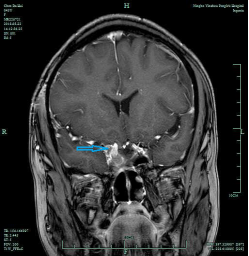

CASE2 病人***女性,46岁,因“视物明显下降2周”入院,入院诊断:垂体侵袭性大腺瘤;

在全麻下行经鼻内镜下垂体瘤切除,术后视力较前明显好转,术后恢复良好, 术后8天出院,出院3月复查仅海绵窦区少许肿瘤残留,继续随访。(红箭头提示垂体大腺瘤,蓝箭头提示术后复查海绵窦有少许肿瘤残留)